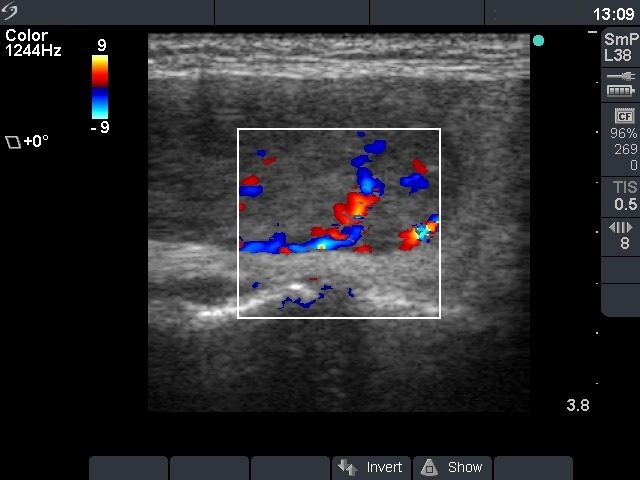

Ultrasonography: the thyroids were echonormal. There was a moderately hypoechogenic nodule displaying both perinodular and intranodular blood flow.